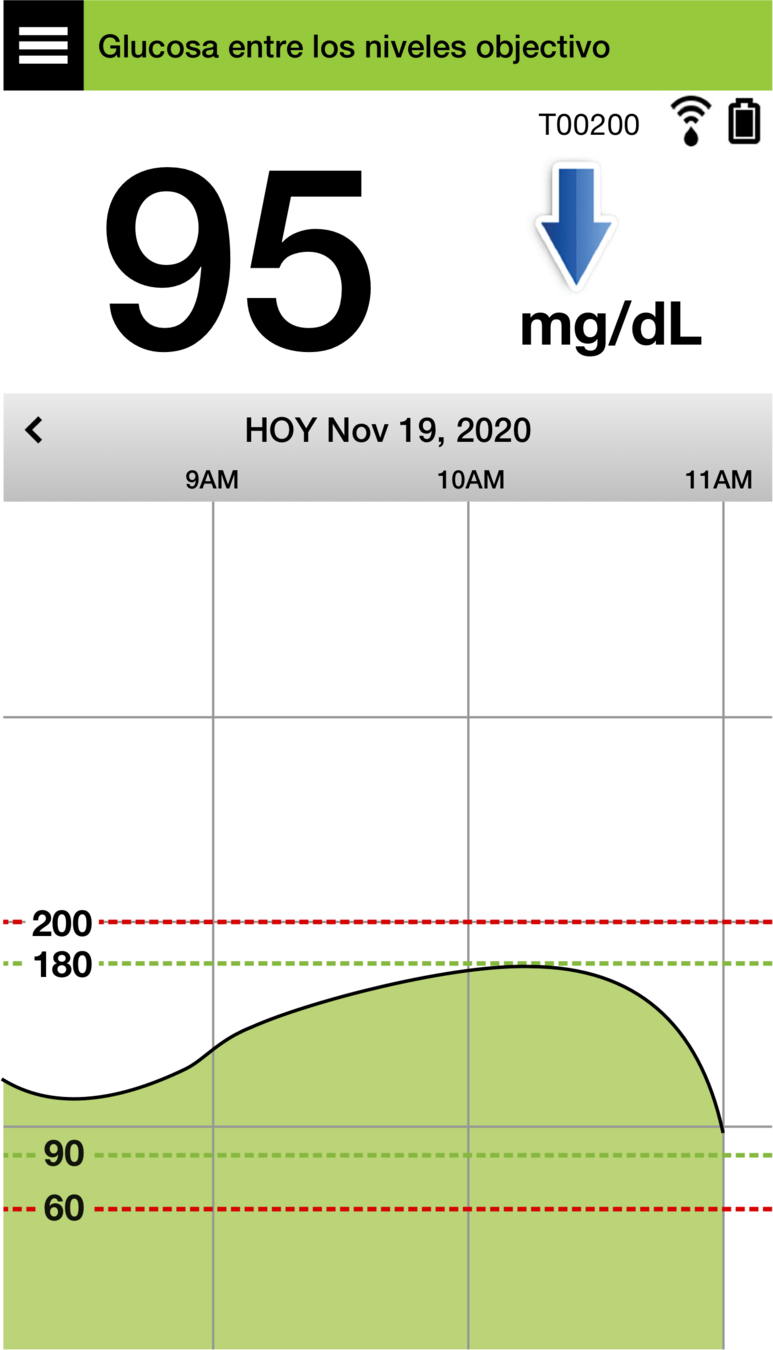

Y, en la parte inferior, se encuentra el gráfico de tendencia de la glucosa.

Las líneas discontinuas rojas indican los niveles de alerta de glucosa alta y baja, y las líneas discontinuas verdes indican el intervalo objetivo.

Todos los eventos que introduzca en la aplicación (como una calibración, comida, ejercicio

o insulina) o las alertas que reciba, se mostrarán en el gráfico de tendencia con un icono.

PANTALLA DE INICIO MI GLUCOSA